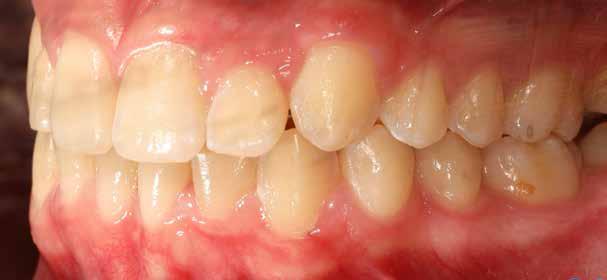

A fix fogszabályozó készülék mindössze 16 hónapos kezelés után került eltávolításra! Páciensünk legnagyobb örömére állcsontműtét nélkül sikerült mind az arcesztétikai, mind a funkcionális rehabilitáció (13–18. képek)